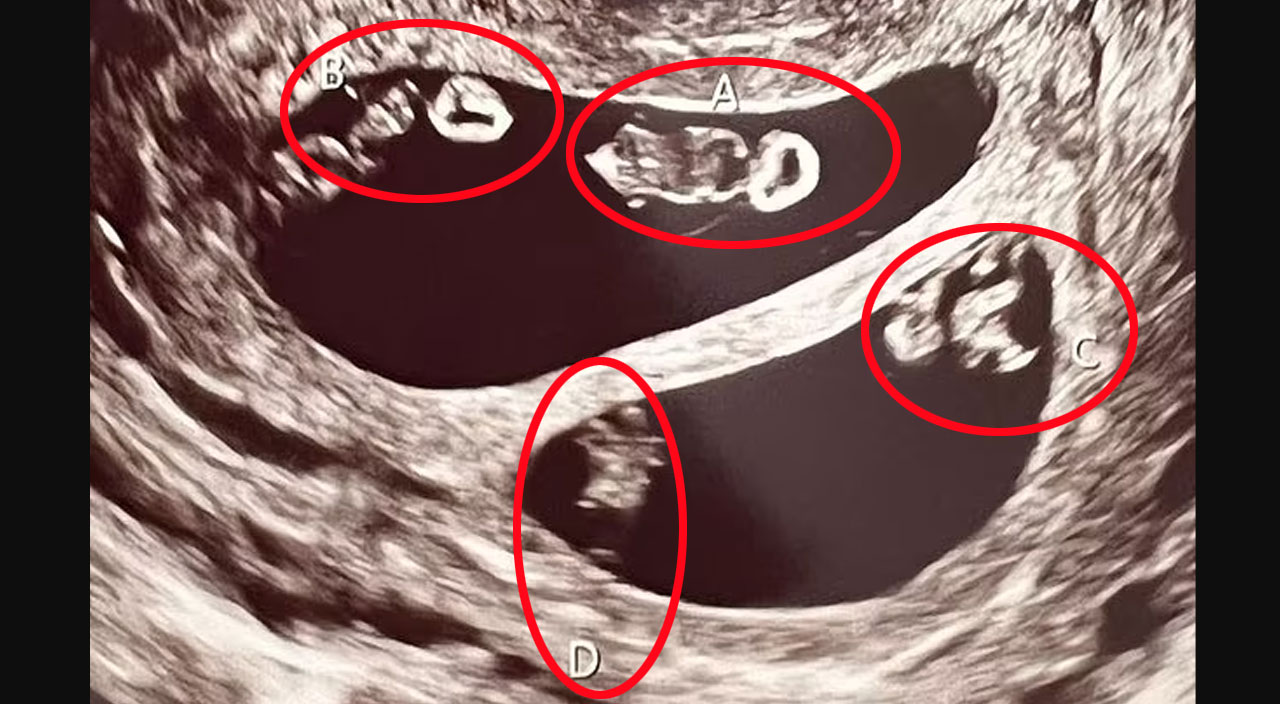

Bu haber kadını şoke ederken bir büyük şaşkınlığı da ultrason teknisyeni yaşadı: Kadın aynı anda birbirinden tamamen ayrı iki ikiz bebeğe hamileydi. Bunun 70 milyonda bir ihtimal olduğu açıklandı.

ABD’nin Massachusetts eyaletinde kuaförlük yapan Ashley Ness’e (35) şubat ayında doktorlar, bir çocuğunun olacağını söyledi. Daha sonra çekilen ultrasonda kadının bir değil dört bebeğinin olacağı ortaya çıktı.